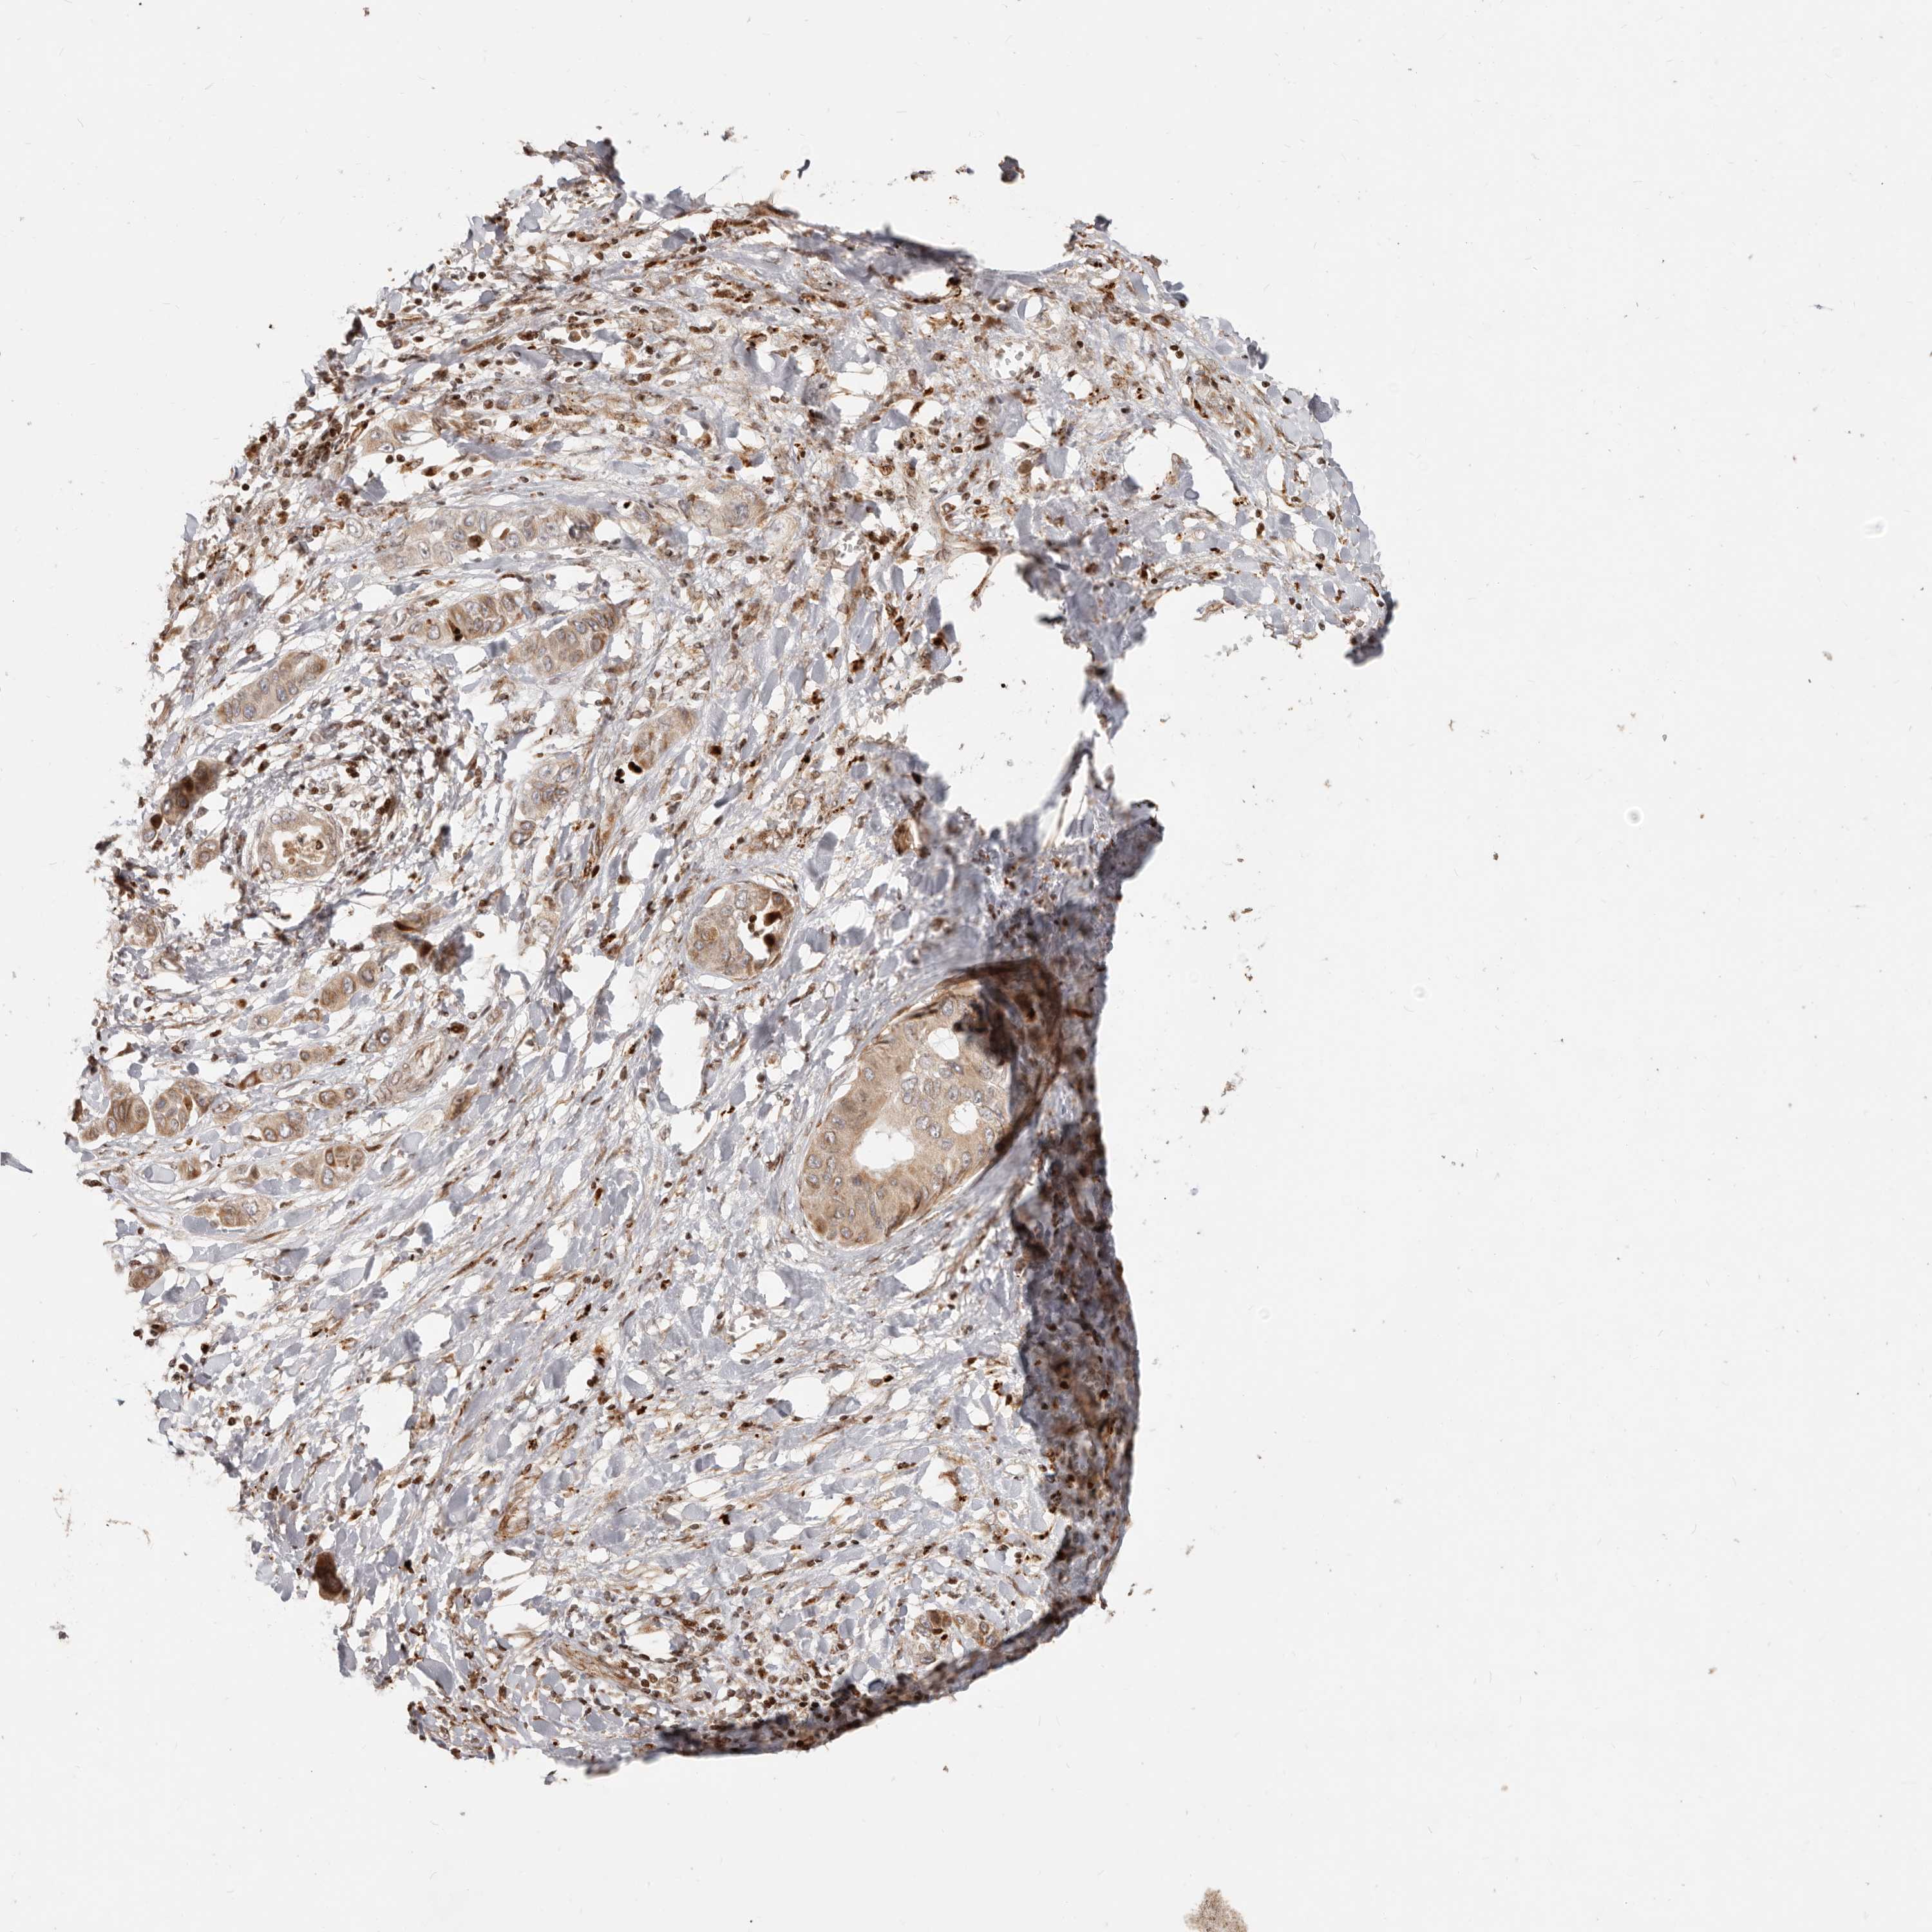

LIVER CANCER - Protein expressioni

A mouse-over function shows sample information and annotation data. Click on an image to view it in a full screen mode. Samples can be filtered based on level of antibody staining by selecting one or several of the following categories: high, medium, low and not detected. The assay and annotation is described here.

Note that samples used for immunohistochemistry by the Human Protein Atlas do not correspond to samples in the TCGA dataset.

Antibody stainingi

Antibody staining in the annotated cell types in the current human tissue is reported as not detected, low, medium, or high, based on conventional immunohistochemistry profiling in selected tissues. This score is based on the combination of the staining intensity and fraction of stained cells.

Each image is clickable and will lead to virtual microscopy that enables deeper exploration of all samples and also displays staining intensity scores, fraction scores and subcellular localization as well as patient and tissue information for each sample.

Antibody HPA019356

Antibody HPA029461

Staining

High

Medium

Low

Not detected

Intensity

Strong

Moderate

Weak

Negative

Quantity

>75%

75%-25%

<25%

None

Location

Nuclear

Cytoplasmic/membranous

Cytoplasmic/membranous,nuclear

Cholangiocarcinoma

Carcinoma, Hepatocellular, NOS